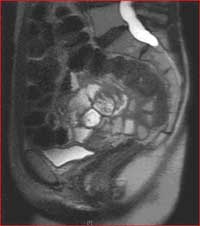

MRI defecography is a painless MRI examination that provides information on the function of the rectum, and the surrounding organs such as the bladder, vagina and small bowel. It analyzes the pelvic muscles, specifically their strength and control.

Functional disorders of the pelvic floor are considered a common clinical problem. Diagnosis and treatment of these disorders, which manifest as nonspecific symptoms such as constipation or incontinence, remain a difficult process. MRI defecography has been shown to aid in detection of functional and morphologic abnormalities of the anorectal region, including the opening of the anal canal, the function of the puborectal muscle, and the descent of the pelvic floor during increased intra-abdominal pressure. MR defecography is also helpful in assessing the anorectal morphology and function in relation to surrounding structures without exposing the patient to ionizing radiation.

Sagital image of the pelvis during MRI defecography